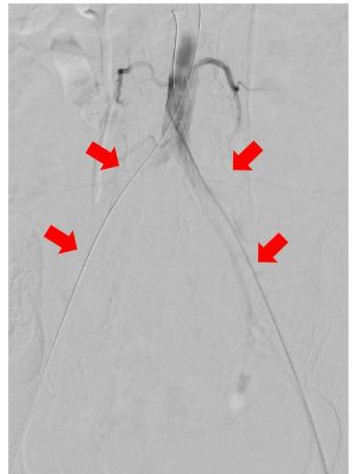

经过CTA证实,伊女士出现的是腹主动脉骑跨栓,从腹主动脉下段分叉开始都出现了不同程度的栓塞,双下肢出现了严重的缺血。

图中箭头所示:术前CTA提示腹主动脉双髂动脉骑跨栓,腹主动脉下段及双髂动脉血流中断

术中DSA:箭头提示双髂动脉血栓栓塞,血流中断

术中DSA:双髂动脉血流恢复